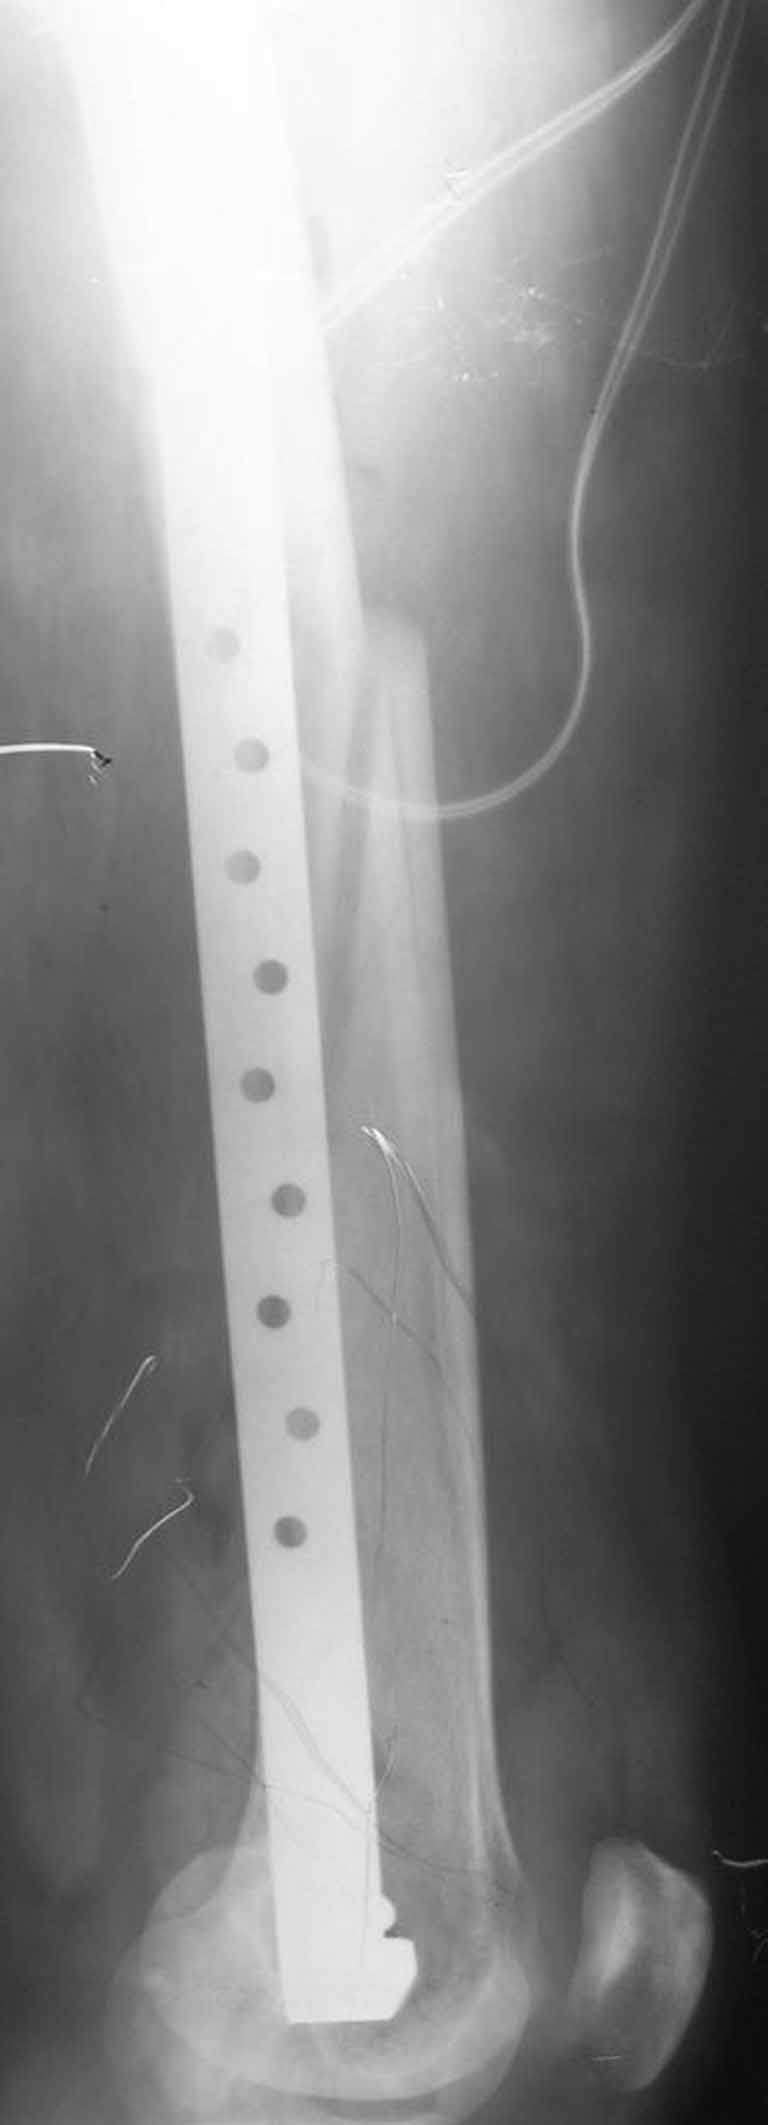

Представляю вам один из наших недавних случаев выполнения малоинвазивного остеосинтеза бедренной кости обычной пластиной 95 градусов. Длина восстановлена с помощью дистрактора (по сути это основная и б(о)льшая часть репозиции). Произведено два небольших доступа, проведена спица направитель. Рентген-контроль для подтверждения достаточной длины/оси (ЭОП использовался в другой операционной). Создание туннеля обратной стороной фиксатора. Поворот фиксатора, введение клинка по спице. Фиксация проксимального и дистального концов пластины.

Получилось очень симпатично, поздравляю и восхищаюсь мастерством.

Хотя закрытый остеосинтез блокированным гвоздем выглядит технически проще, особенно при диафизарных переломах. Не говоря о биомеханических преимуществах внутрикостного имплантата, еще меньшей инвазивности, возможности динамизации при проблемах со сращением... Стоимость гвоздей и пластин сопоставимая, на рынке есть масса отечественных предложений.

В приложении - недавний перипротезный перелом.

Методичка по закрытому интрамедулярному остеосинтезу при дистальных переломах бедра тут.